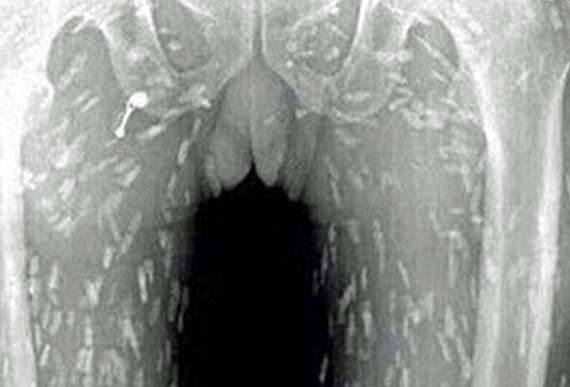

▼男子在就医后被转往广州市第八人民医院,医生认为他应是吃了受到污染的生鱼片才会被条虫寄生。条虫只存在淡水鱼类中,生鱼片中非常常见的「鲑鱼」便是其中一种。